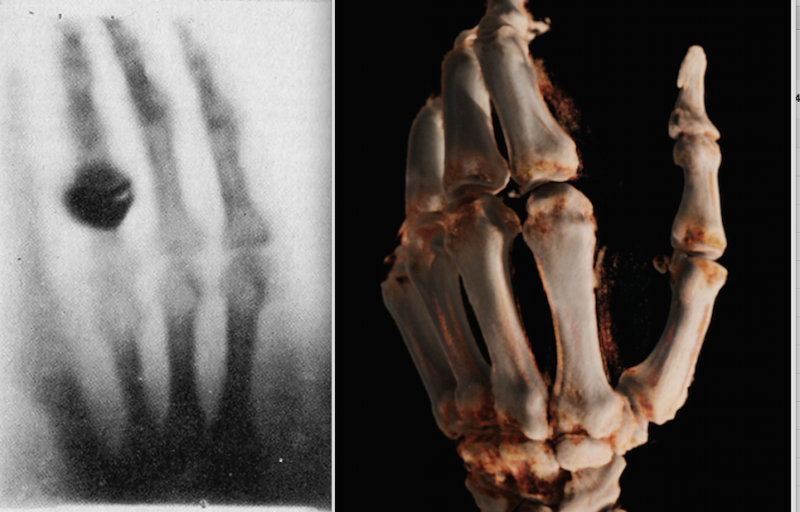

Left, the first X-ray ever made of Roentgen's wife's hand in 1895. Right, a cone-beam CT 3-D reconstruction of a hand in 2015 using a new robotic digital radiography (DR) X-ray system.

Two weeks after Wilhelm Roentgen first discovered what he termed as X-rays in 1895 (he used the mathematical “X” to describe something unknown), he produced the first X-ray image of his wife’s hand. This image was the first medical imaging photo published in the first scientific article on medical imaging in December 1895. The breakthrough technology rapidly revolutionized medicine and earned Roentgen the first Nobel Prize in physics in 1901.

Being the symbol of the birth of radiology and modern medical imaging, this image of Roentgen’s wife’s hand was the first thing I thought of when I ran across an image of a cone-beam computed tomography (CT) 3-D reconstruction of a hand created by Siemens' new Multitom Rax robotic X-ray system. The comparison of hand X-rays now and then is a simple comparison of how far X-ray technology has advanced, from a fuzzy image of phalanges to a surgical, photo-quality view of the bone.